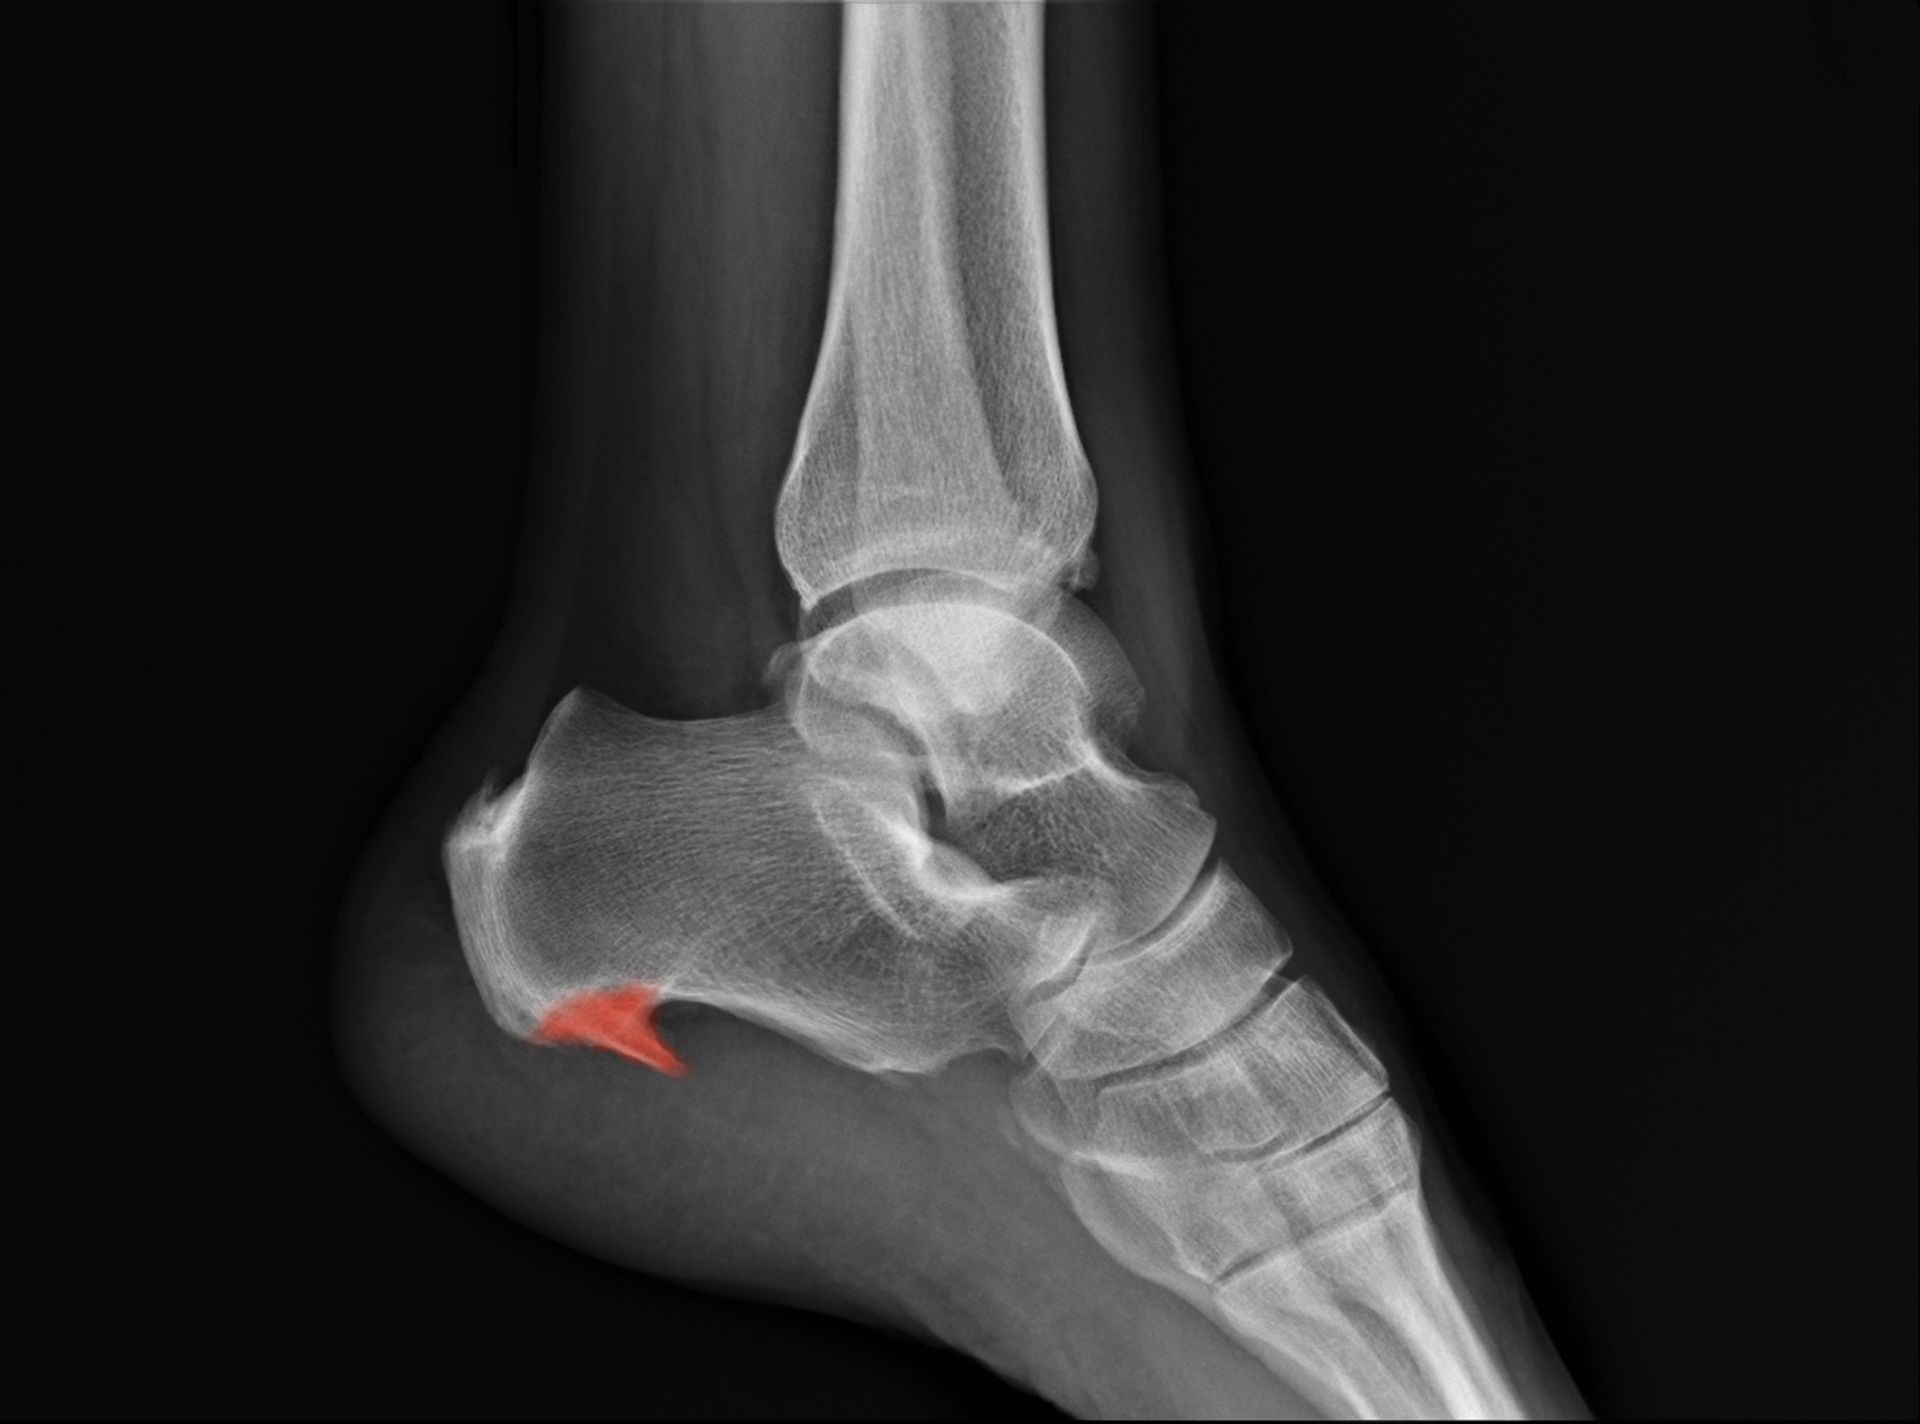

Podiatric medicine focuses on the diagnosis and treatment of conditions affecting the foot, ankle, and lower leg. Podiatrists use proven, hands-on approaches to evaluate symptoms, identify the source of pain, and provide effective treatment options. Care may include preventive services, custom orthotics, therapeutic treatments, medications, and surgical solutions when needed, all aimed at improving comfort, mobility, and overall foot health.